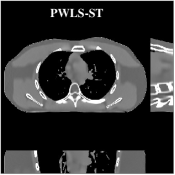

We reconstructed the chest volume from helical CT data. For PWLS-EP, we used the same parameter settings as used for this data in prior work [50]. Initializing with the PWLS-EP reconstruction, we ran the PWLS-ULTRA () method with the weights for outer iterations with iterations of the image update step and subsets. We performed clustering once every outer iterations. We chose and for PWLS-ULTRA to obtain good visual quality of the reconstruction. We used the transforms learned from the XCAT phantom volume with to obtain reconstructions with PWLS-ULTRA for the clinical chest CT data. The supplement shows that transforms learned from the XCAT phantom provide similar visual reconstructions as transforms learned from the PWLS-EP reconstruction of the chest data. This suggests that the transform learning algorithm may extract quite general and effective image features without requiring a very closely matched training dataset, which is a key distinction from the PICCS and ndiNLM-type methods [8, 9, 10, 11, 12, 13].

Fig.Β 7 shows the reconstructions (shown for the central axial plane in the 3D volume) for FDK (provided by GE Healthcare), PWLS-EP (corresponds to Fig.Β 8(a)), and PWLS-ULTRA with (corresponds to Fig.Β 9(a)). The PWLS-ULTRA reconstruction has lower artifacts and noise. Moreover, the image features and edges are better reconstructed by PWLS-ULTRA than by PWLS-EP or FDK.